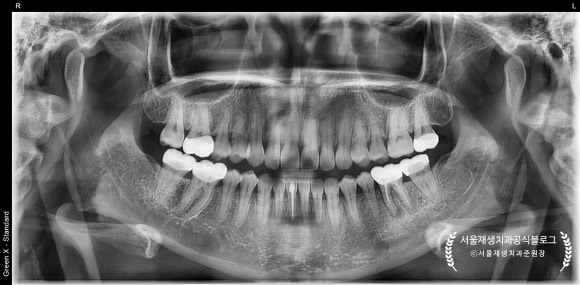

파노라마 엑스레이를 먼저 볼까요?

(정확한 진단에는 전체를 보는 눈이 필수입니다!)

왼쪽 아래 어금니 뿌리 주변이 심상치 않네요...

확대해보겠습니다.

파노라마를 확대해보니,

뿌리 쪽으로 까맣게 뼈가 녹아내린 모양이 관찰됩니다.

보다 정확한 진단 및 상황파악을 위해

치근단엑스레이를 추가로 촬영하였습니다.